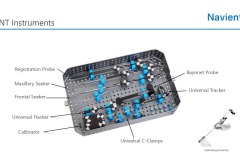

Cranial, Biopsy, Spine, ENT

Tracking system

• Infrared optical tracking system

• Live video stream

• 0.2mm calibration accuracy

• Permanent markers

• Reusable and sterilizable instruments